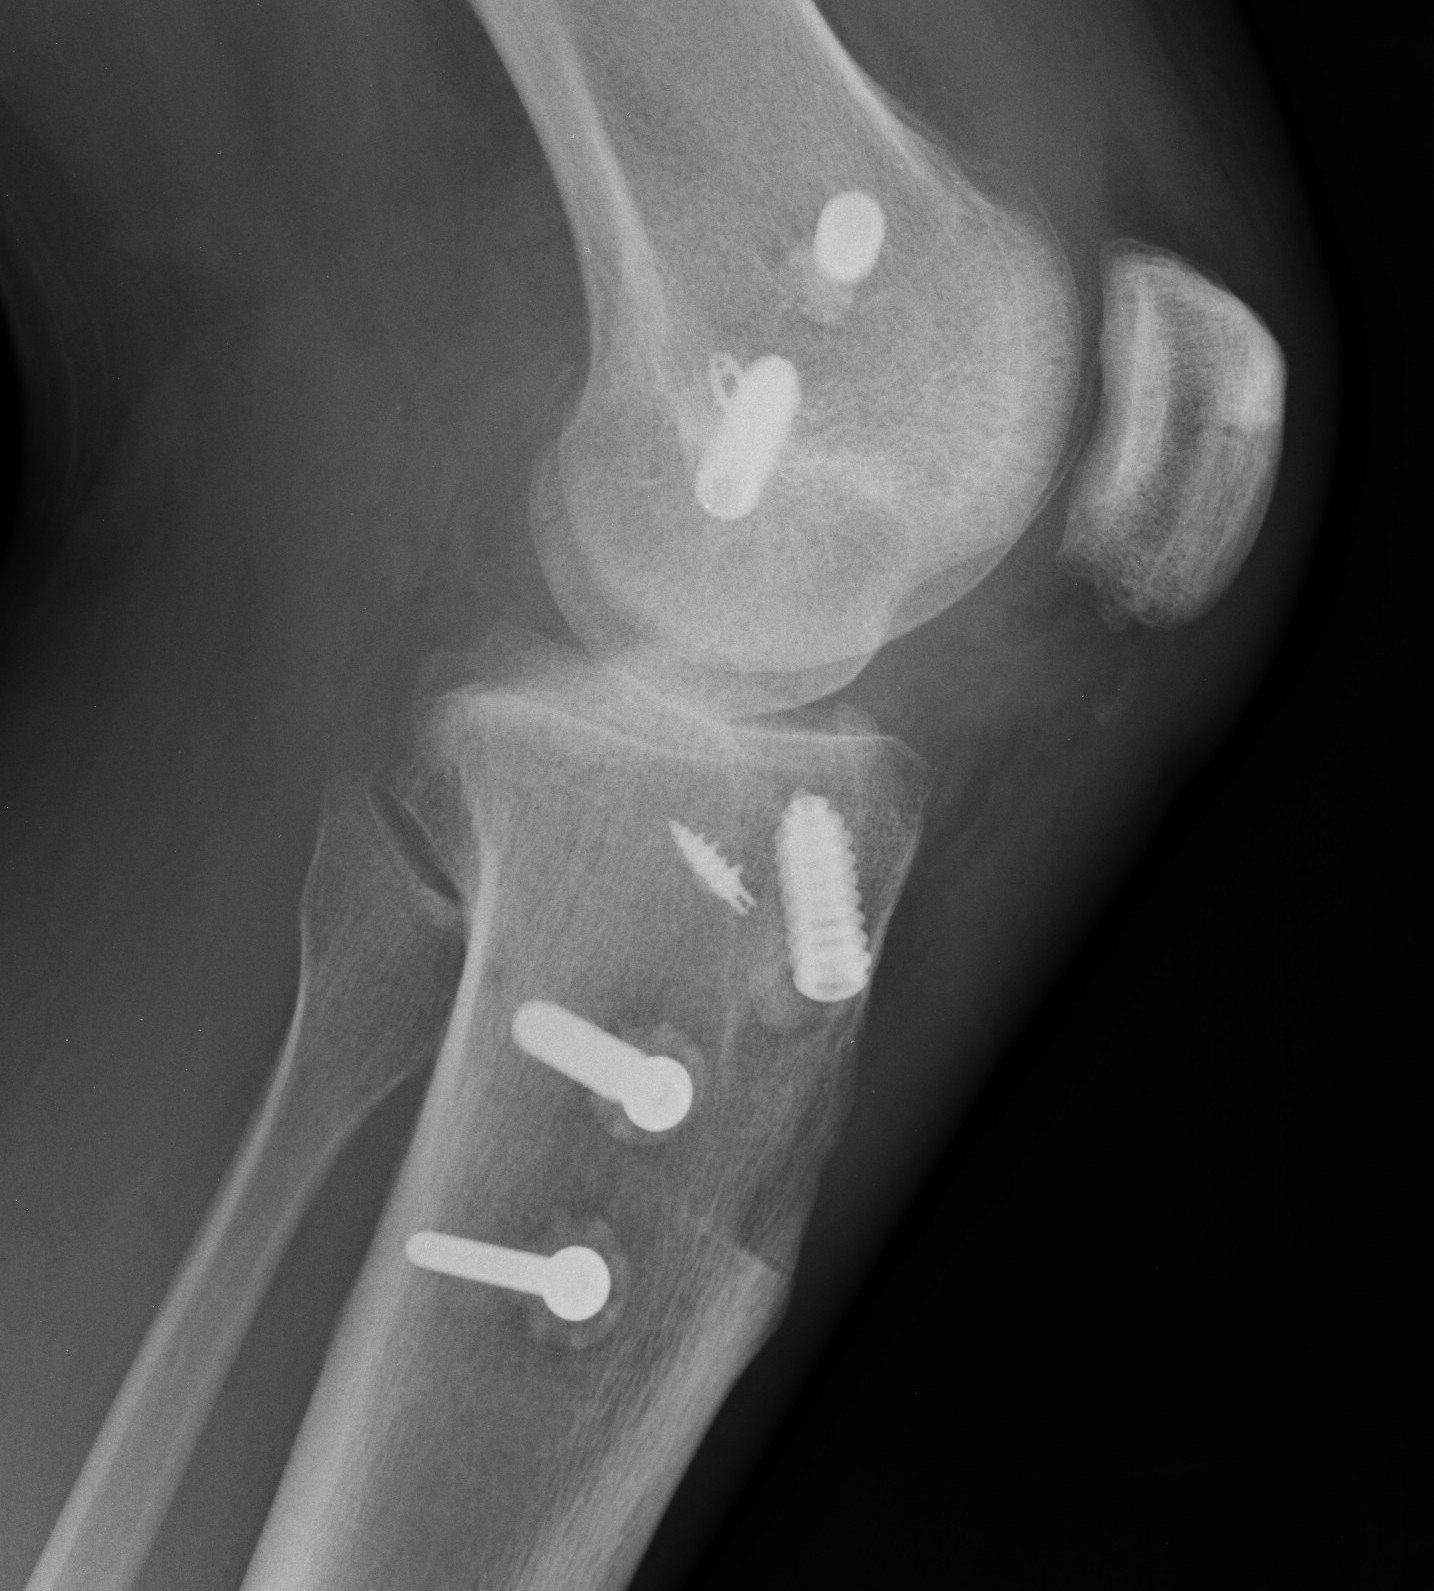

Xray following PCL reconstruction, LCL and politeus reconstruction. CT demonsrating popliteus and LCL tunnels